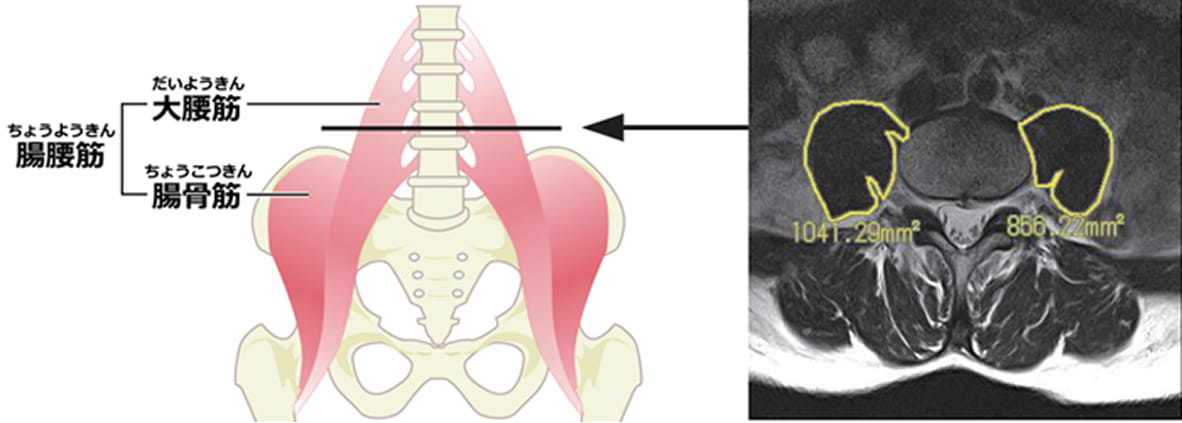

背骨全てを検査することに加えて大腰筋の面積を計測します。

筋肉の衰えでも、背骨への負担は変わってきます!

※大腰筋:大腿骨と背骨をつないでいる筋肉で、姿勢を維持するために必要な筋肉